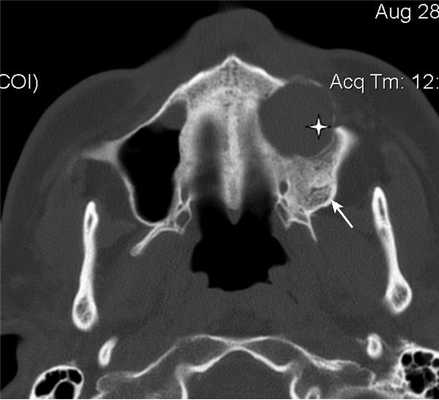

При воспалительных изменениях в ретроантральной жировой клетчатке верхнечелюстной пазухи на РКТ повышаются денситометрические значения ее плотности [10]. При одностороннем процессе отмечается выраженная асимметричность значений плотностей (рис. 4).

Рис. 4. Рентгеновская компьютерная томограмма околоносовых пазух. Аксиальная проекция, костное окно.